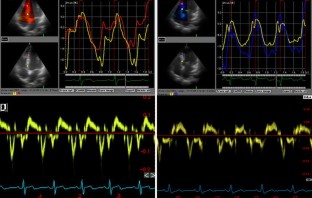

Eighty patients (mean age: 57.2 ± 11.5 years) referred for cardiac catheterization were studied. Patients were divided into 2 groups according to LVEDP (group 1: LVEDP > 20 mmHg, n = 39 patients; group 2: LVEDP ≤20 mmHg, n = 41 patients). From the mitral inflow, peak E velocity was calculated. With tissue Doppler echocardiography, early diastolic velocity (E′) measured from the septal, lateral, inferior and lateral mitral annulus and mean value of E′ and E/E′ ratio were calculated. The time difference between onset of mitral inflow and onset of early diastolic mitral annulus velocity (TE′-E) was calculated. From the apical chambers, the peak systolic strain value of 16 left ventricular (LV) segments was measured and the mean of these 16 segments was calculated and referred to as mean systolic strain index.

Fig. 1

Fig. 2

Fig. 3

Fig. 4